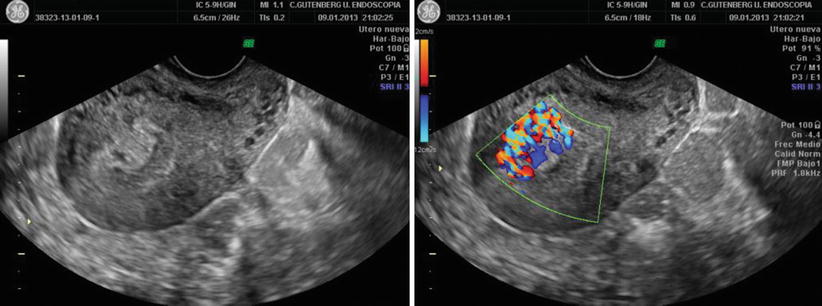

Ultrasonographic Patterns Of Rpoc Gutenberg Classification A Type 0 Download Scientific Diagram